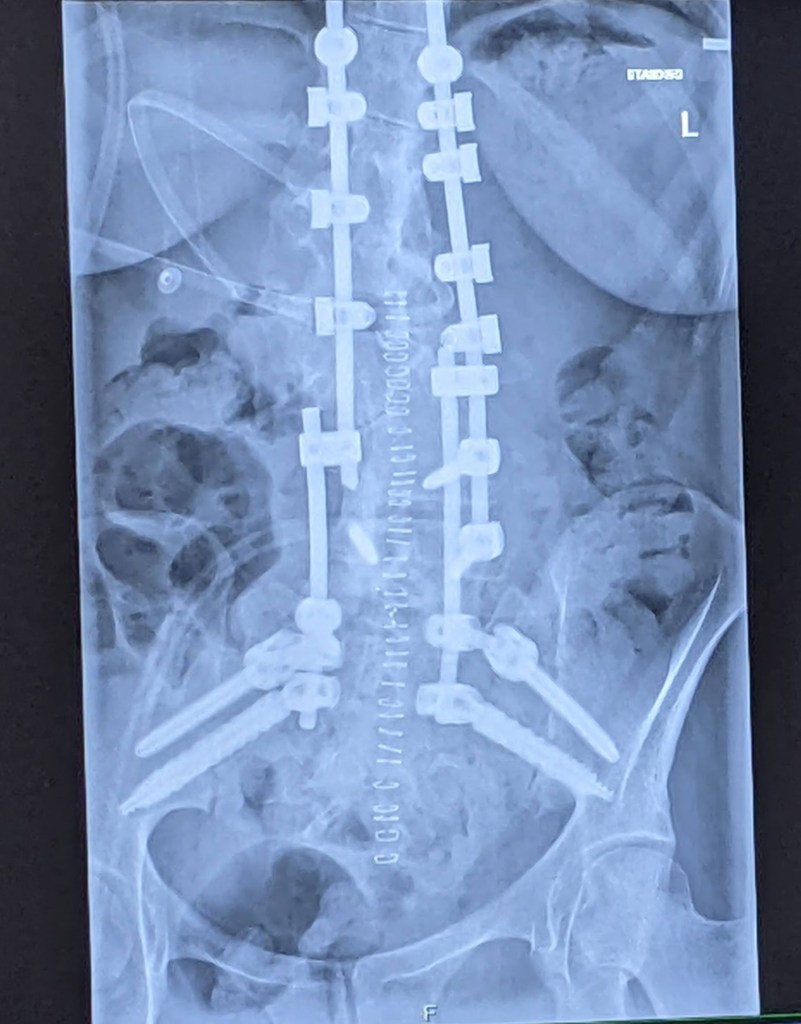

I know my post-op x-ray above isn’t as clear as the pre-op one – I had a wound-vac and staples in at the time. To summarize – in the surgery they took out my S1 screws from 2.5 years ago due to their proximity to S1 nerve root and repositioned the one on the right side (they actually just left out the left S1 screw because there wasn’t space, my vertebrae are weird). Then they removed the S2 AI screws and repositioned them with this new technology of 3D printed screws that are supposed to more successfully fuse to bone. Then they put in more screws and bone graft to fuse my sacroiliac joint and hopefully better distribute the weight of my spine across my pelvis. They tracked my nerve signals throughout the procedure and on my left side, my signals actually improved, which is best case scenario!